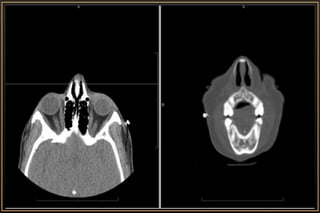

Computed Tomography

Major Considerations

• Slice thickness

• Imaging plane – Axial / Coronal / Sagittal

• Tissue window – Soft or Brain / Bone

• Contrast enhancement – Iohexol (46% Iodine)

• Modification of CT procedure

• Most versatile,informative • Bony detail or calcification • Detect metallic foreign body • Inability to distinguish between pathological soft tissue masses which are radiologically isodense • Exposure to radiation - Cataract Computed Tomography

Computed Tomography Major Considerations •Slice thickness • Imaging plane – Axial / Coronal / Sagittal • Tissue window – Soft or Brain / Bone • Contrast enhancement – Iohexol (46% Iodine) • Modification of CT procedure • Orbit with Brain CT

• #14 Slide Thickness • Spatial resolution of a CT depends on slice thickness. • The thinner the slice, the higher the resolution. • Usually, 2mm cuts are optimal for the eye and orbit. • In special situations (like evaluation of the orbital apex/Optic Nerve), thinner slices of 1mm/1.5mm can be more informative. Modification of CT procedure • Certain cases may require special modifications during the scanning procedure to aid diagnosis. • In a case of orbital venous varix, it is important to request for special scans (with contrast) while the patient performs a Valsalva maneuver. Simultaneous brain CT • Suspected neurocysticercosis with orbital involvement. • Head injury with orbital trauma • Optic nerve meningiomas